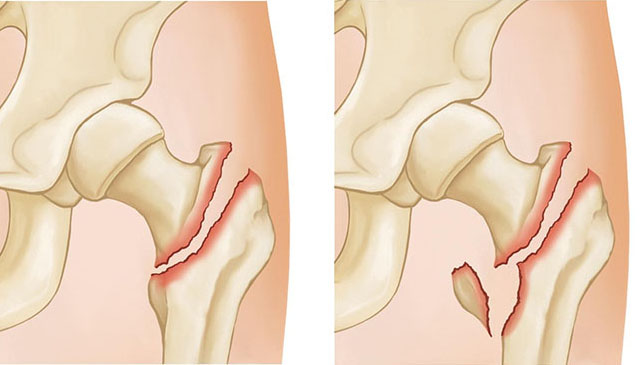

Intertrochanteric fractures occur below the femoral neck in a broader region between the greater and lesser trochanters. The greater trochanter is the bump you feel on the side of your hip. There may be two, three, or even more fracture fragments.

two- and three-part intertrochanteric fractures

Two-part (left) and three-part (right) intertrochanteric fractures